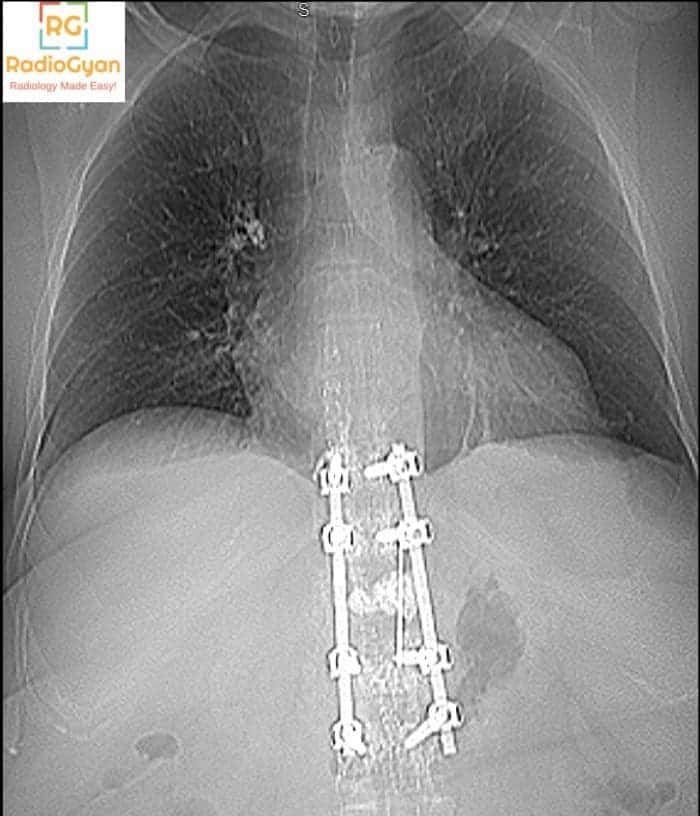

PA chest radiograph of adult patient with over-penetration

it shows vertebral fixation for T10 to L2 by nails and plates

the cardio/thoracic ratio is slightly increased for correlation with echocardiography

right calcified hilar LN

Normal both lung fields

no pleural effusion

central mediation structures

both diaphragmatic copulae are smooth and normal in position

the bony thoracic cage show no gross abnormalities

Cemnt from vertebra plasy in right pulm artery embolism